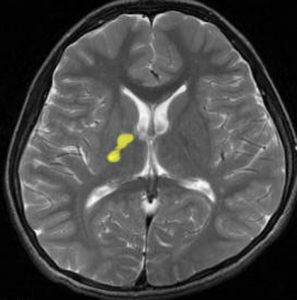

germinomaの視床浸潤:ミッキーマウスの耳

松果体ジャーミノーマは両側視床に浸潤して視床浮腫を生じます。真ん中に第3脳室後半部の割れ目が残っているのが特徴的な所見です。ミッキーマウスの耳みたいになります。かなり特異的な所見であり診断に有用です。右下は治療後です。